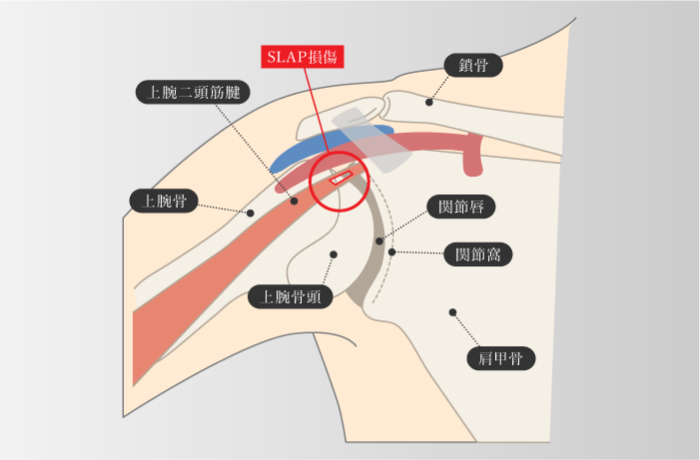

SLAP損傷

スラップ損傷

SLAP損傷

スラップ損傷

-

上腕二頭筋腱と関節上腕靭帯がつながっている関節唇上部(SLAP)に引っ張られる力やひねられる力などの負荷がかかり、関節唇が傷ついたり、裂けてしまったりすること